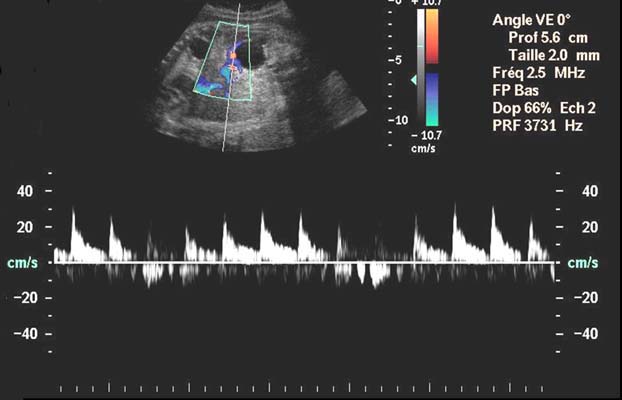

Flux-Segmentaire